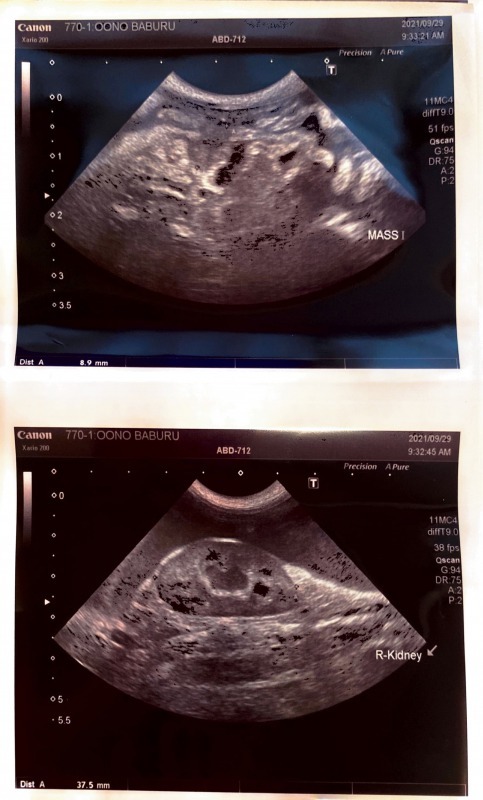

2021年9月29日

・超音波検査

・貯留液検査

をしてもらい、ウエットタイプだけだと思っていたのですが、リンパ節が少しだけ大きい(9mm)といわれ、ドライタイプとの混合タイプだと判明しました。

(超音波)